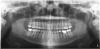

Panoramic

A digital panoramic radiograph (Figure 2) is indicated for circumstances in which intraoral imaging is not practical, as in patients who cannot open their mouths due to trismus or in those who cannot tolerate having a sensor or film in their mouth due to severe mucositis following radiation therapy for cancer. Advantages of panoramic imaging are that it quickly provides broad coverage of facial bones and teeth, it is convenient for both dental practitioner and patient, and is a helpful visual aid in patient education and case presentation.

(2.) Panoramic radiographs are options when intraoral radiography is impractical or additional diagnostic information is required.

Figure 2